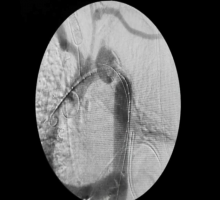

A 64-year-old man was found to have a pseudoaneurysm associated with coarctation at the anastomosis of a previous descending thoracic aortic coarctation repair. An endograft alone would not achieve an adequate seal in zone 2 and risked a worsening of the high pressure gradient across the coarctation. A left carotid subclavian transposition was performed initially. An ascending aorta-to-descending aorta bypass followed by ascending aorta-to-left common carotid artery bypass was then performed. Next, a 34 x 30 x 150 Relay endograft (Bolton Medical, Sunrise, FL, USA) was placed from zone 2 to the mid-descending thoracic aorta. Postoperative computed tomography scan demonstrated an intact repair without endoleak. The patient had an uneventful hospital course and was discharged on postoperative day nine.

A hybrid approach allows for the successful repair of a descending aortic pseudoaneurysm with coarctation.